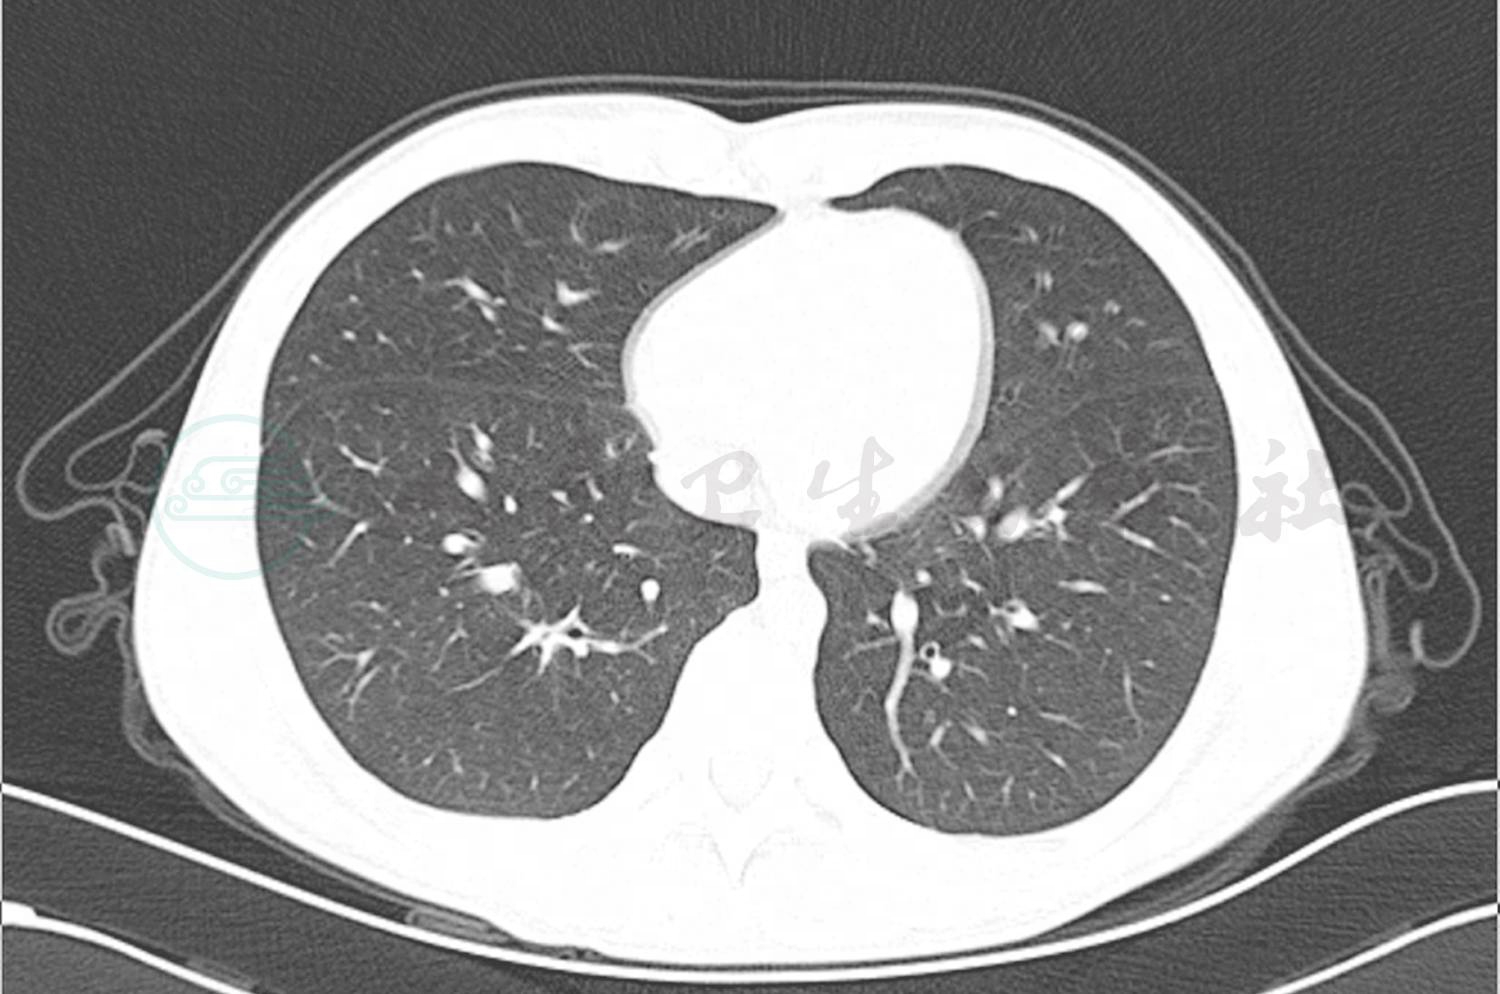

转入笔者科室立即完善相关病原学检查提示GM试验阴性,1,3-β-D葡聚糖 <10µg/L,痰培养及血培养均阴性,PPD 阴性,结核斑点试验(T-spot)阴性,以上检查均未找到明确病原体。入院第5天完善纤维支气管镜检查,镜下示(图3)右肺下叶B10亚段可见大量黄白色类干酪样物质阻塞及坏死黏膜附着管壁,予毛刷刷检,刷检时黏膜有出血,予万分之一盐酸肾上腺素冲洗止血,将刷检物质送病理检查。根据镜下改变,高度怀疑支气管内膜结核及真菌感染。经胸科医院会诊,建议诊断性抗结核治疗,但家属拒绝。给予患儿伏立康唑抗真菌治疗,7天后体温恢复平稳,无咯血,复查肺CT(图4)提示右肺下叶后底段支气管旁高密度团块影较前减小。入院第12天病理结果回报(图5)提示炎性渗出坏死物及霉菌。

图3 入院第5天支气管镜下改变